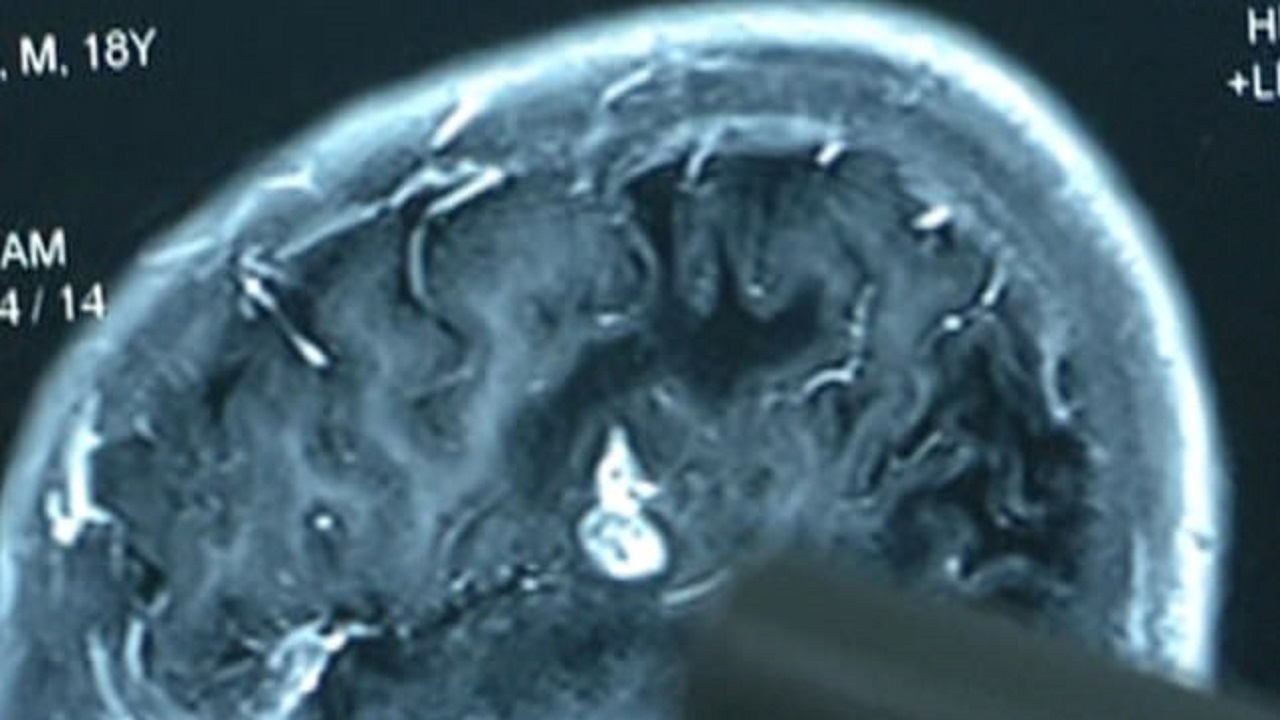

جی پلاس، جراحان چینی کرمی ۱۲.۷ سانتی متری را که به مدت ۱۷ سال در مغز یک بیمار زندگی می‌کرد بیرون کشیدند. این مرد ۲۳ ساله که از سن ۶ سالگی از ناحیه دست و پا احساس کرختی می‌کرد اخیرا به دلیل بی حسی در قسمت بالاتنه خود در بیمارستان بستری شده بود. پزشکان پس از انجام آزمایش سی تی اسکن این انگل را در مغز این جوان مشاهده کردند. این عمل جراحی روز سه شنبه در بیمارستان «ووچانگ» واقع در استان جیانگسو انجام شد.

بنا به گفته پزشکان مصرف گوشت خام یا گوشت نیمه خام مانند قورباغه یا مار موجب ایجاد انگل در بدن این بیمار شده است. مرد ۲۳ ساله که هویتش «چِن» اعلام شده به پزشکان گفت که از ۱۷ سال پیش در دست و پاهایش احساس کرختی می‌کرده است. او همچنین گفت طی این مدت دچار سردرد و برخی اوقات حالت تهوع می‌شده است. این مرد جوان که با تلویزیون محلی جیانگسو مصاحبه می‌کرد گفت که والدینش اصرار داشتند به بیمارستان مراجعه کند، اما او تمام این نشانه‌ها را ناشی از بیماری ژنتیکی می‌دانست.